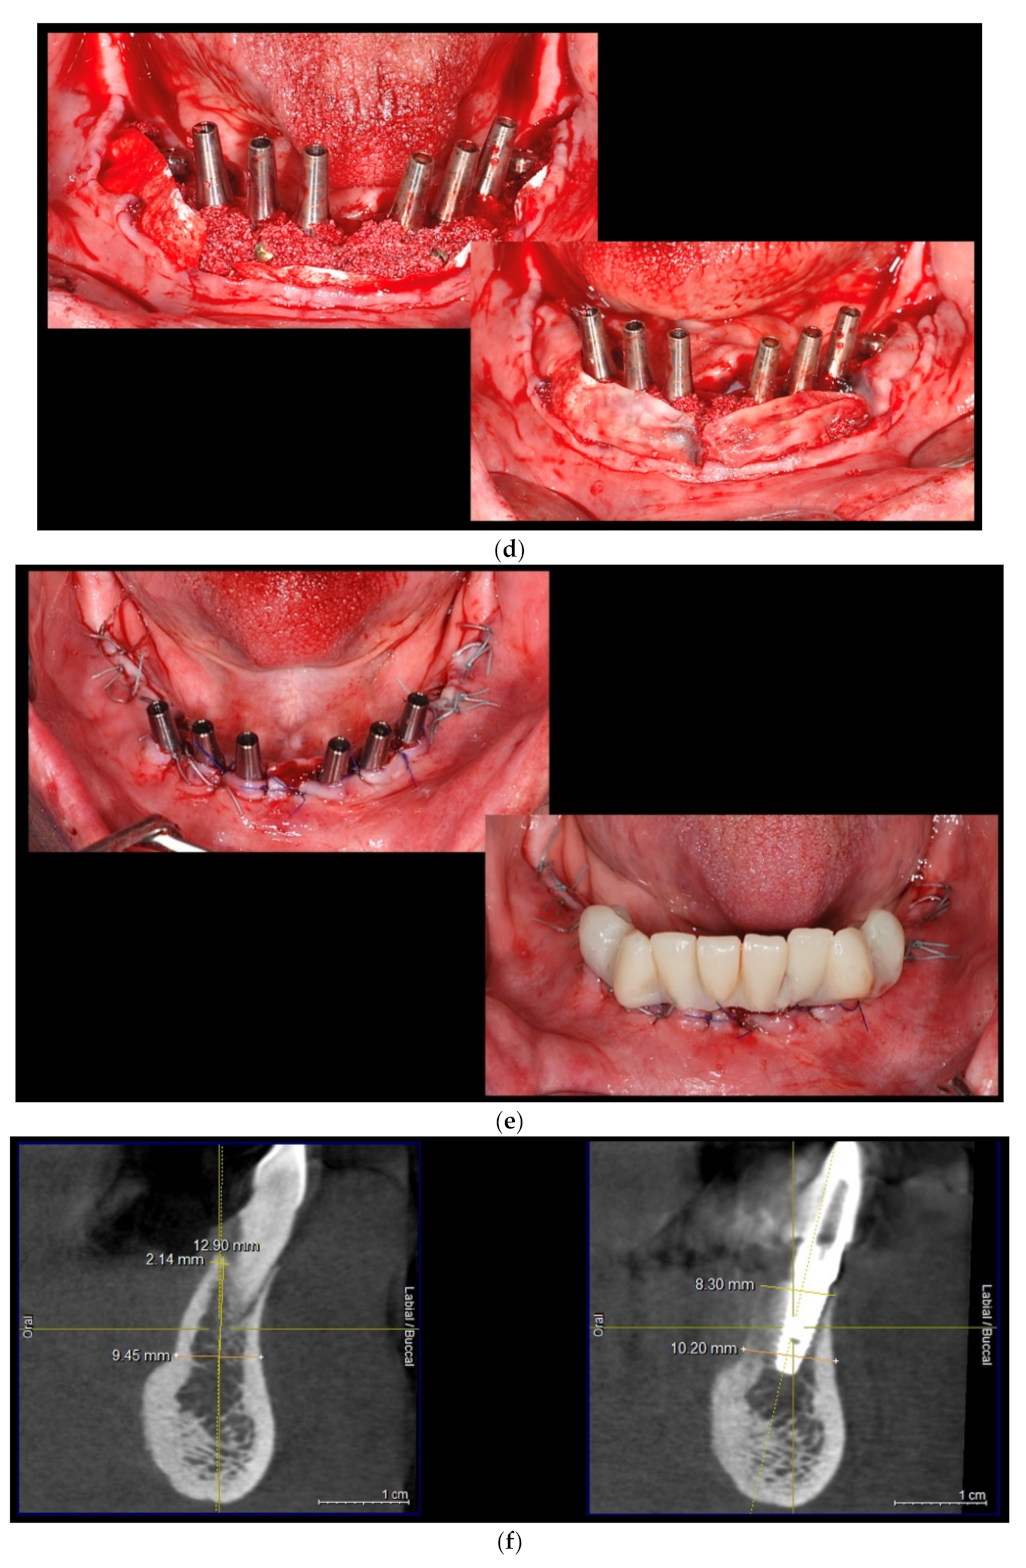

Intraoral view aspects and CBCT images of the implant sites, from a patient included in the test group, are presented in Figure 1a–o (reconstruction of the implant sites by S-GBR technique with porcine-derived xenograft material).

Figure 1.

(a) A.C., aged 65. Preoperatory intraoral view. (b) Preoperative CBCT images and alveolar bone parameters measured with Sidexis XG/ DVT (Densply/Sirona) software. (c) Intraoral view after the insertion of osteosynthesis screws and implants. (d) Intraoral view after the mandibular alveolar reconstruction with S-GBR technique and porcine xenograft. (e) Postoperative intraoral view after wound suture and temporary loading. (f) Alveolar bone width values measured at baseline (left) and at 6 months follow-up with Sidexis XG/ DVT software (Densply/Sirona). (g) Alveolar bone width values measured at baseline (left) and at 6 months follow-up with Sidexis XG/ DVT software (Densply/Sirona). (h) Alveolar bone width values measured at baseline (left) and at 6 months follow-up with Sidexis XG/ DVT software (Densply/Sirona). (i) Alveolar bone width values measured at baseline (left) and at 6 months follow-up with Sidexis XG/DVT software (Densply/Sirona). (j) Alveolar bone osteodensity values measured at baseline (left) and at 6 months follow-up (right) (implant site 4.1). (k) Alveolar bone osteodensity values measured at baseline (left) and at 6 months follow-up (right) (implant site 4.5). (l) Alveolar bone osteodensity values measured at baseline (left) and at 6 months follow-up (right) (implant site 3.2). (m) Alveolar bone osteodensity values measured at baseline (left) and at 6 months follow-up (right) (implant site 3.5). (n) Preloading intraoral view. (o) Postloading intraoral view.